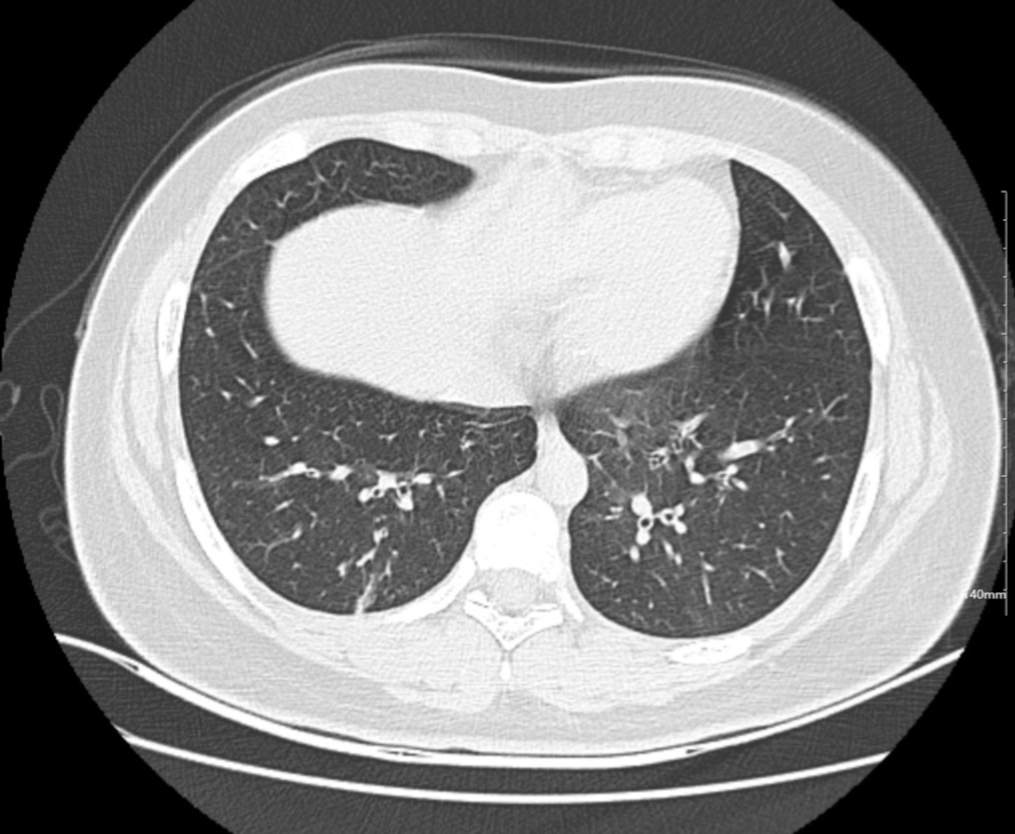

肺部CT:

百日咳肺炎CT 表现

支气管血管束增粗且伴 < 2 个肺叶的磨玻璃密度影, 多提示为单纯性百日咳肺炎。(下图:支气管血管束增粗, 两肺下叶基底段少许磨玻璃密度影)

如出现肺内支气管血管束增粗, 伴≥3 个肺叶斑片影、亚段性实变及支气管气象时, 提示患儿病情较重,可能合并其他感染。